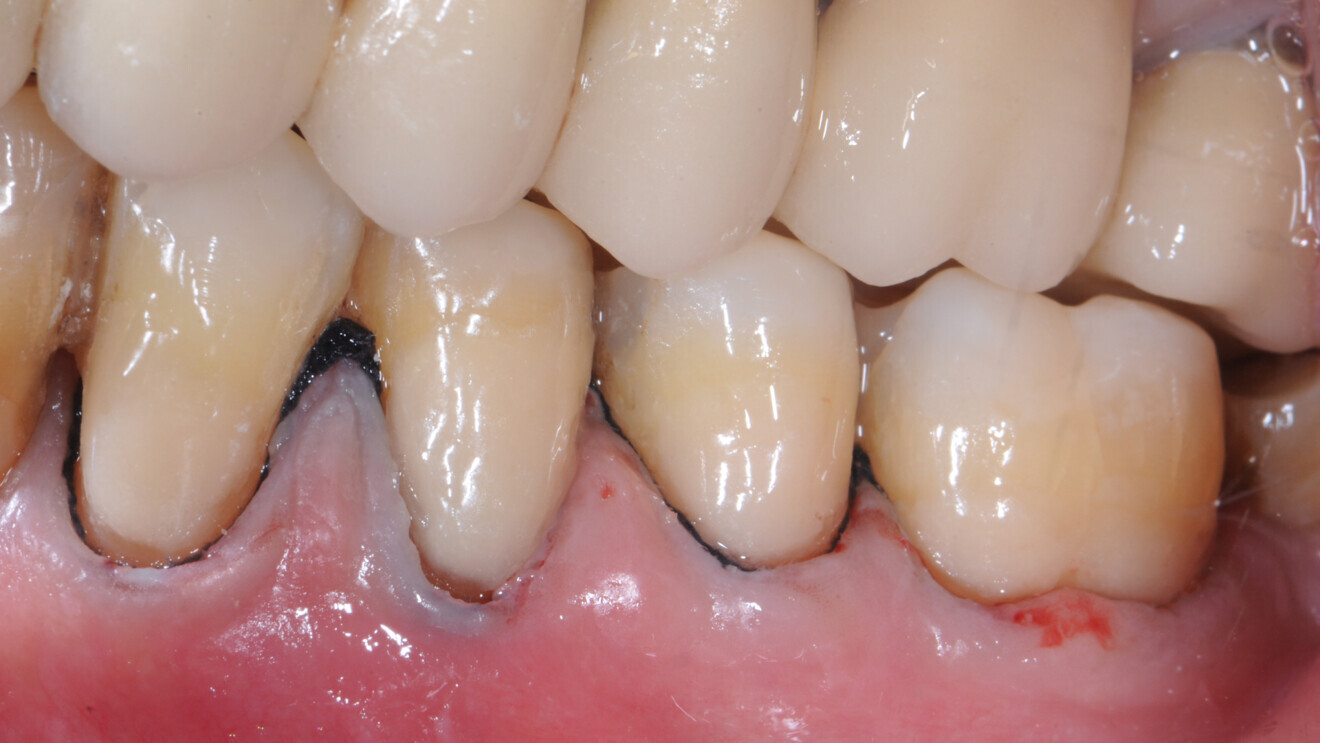

En raison de la perte osseuse parodontale, les patients âgés présentent souvent des espaces interdentaires ouverts qui sont prédisposés aux lésions carieuses radiculaires (Fig. 1). Ces patients doivent veiller à une hygiène de ces espaces au moyen de brossettes interdentaires et d’un dentifrice fluoré.

Fig. 1 : Les racines exposées sont prédisposées au risque carieux ; elles se déminéralisent plus tôt et plus rapidement, car la dentine ou le cément n’est pas protégé par l’émail ou l’alvéole.

Fig. 4a : Dans les études cliniques randomisées et contrôlées, les verres hybrides montrent des résultats prometteurs pour la restauration des lésions cervicales. a) Lésion cervicale non carieuse, avant traitement,